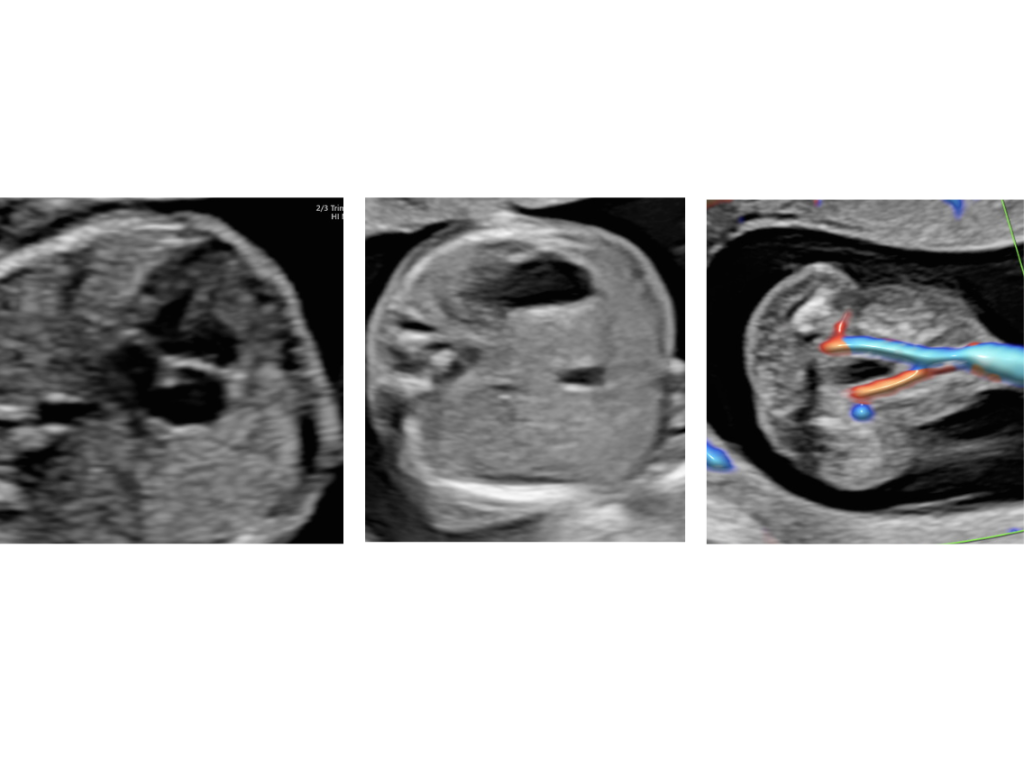

בדיקת אולטרסאונד המתבצעת בגישה בטנית, נרתיקית או משולבת – בהתאם לצורך. מטרתה היא לאתר מומים מבניים משמעותיים כבר בשלבים מוקדמים, כאשר רוב איברי הגוף כבר מפותחים וניתנים להדגמה.

בין האיברים הנבדקים: מוח, פנים, לב וכלי הדם הגדולים, ריאות, איברי הבטן (קיבה, מעי, כבד, כיס מרה, כליות ושלפוחית השתן), עמוד השדרה וגפיים עליונות ותחתונות.

סקירה זו מבוצעת לרוב בגישה בטנית, ולעיתים תתווסף גם בדיקה נרתיקית להשלמת ההדמיה.

נבדקות בה אותן מערכות שנבדקו בסקירה המוקדמת, לצד איברים נוספים אשר מתפתחים בשלבים מאוחרים יותר, וכן ניתן להבחין בפרטים קטנים יותר הודות לגדילתו של העובר.

גולגולת, מוח, פנים, אף, שפתיים, ארובות עיניים

בית החזה: ריאות, לב וכלי דם גדולים

בטן: דופן הבטן, קיבה, כיס המרה, מעי, כליות, שלפוחית השתן

עמוד השדרה, גפיים עליונות ותחתונות